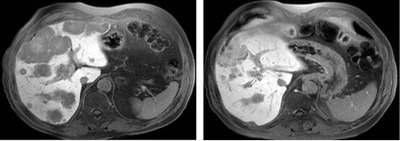

tochtergeschwulst

MRI mit zahlreichen Tochtergeschwülsten (Metastasen) in der Leber eines Patienten mit Darmkrebs. Ausgangsbefund vor Durchführung einer SIRT (linkes Bild) sowie Verlaufskontrolle 3 Monate nach der minimalinvasiven Behandlung (rechtes Bild) mit Nachweis eines deutlichen Therapieansprechens.